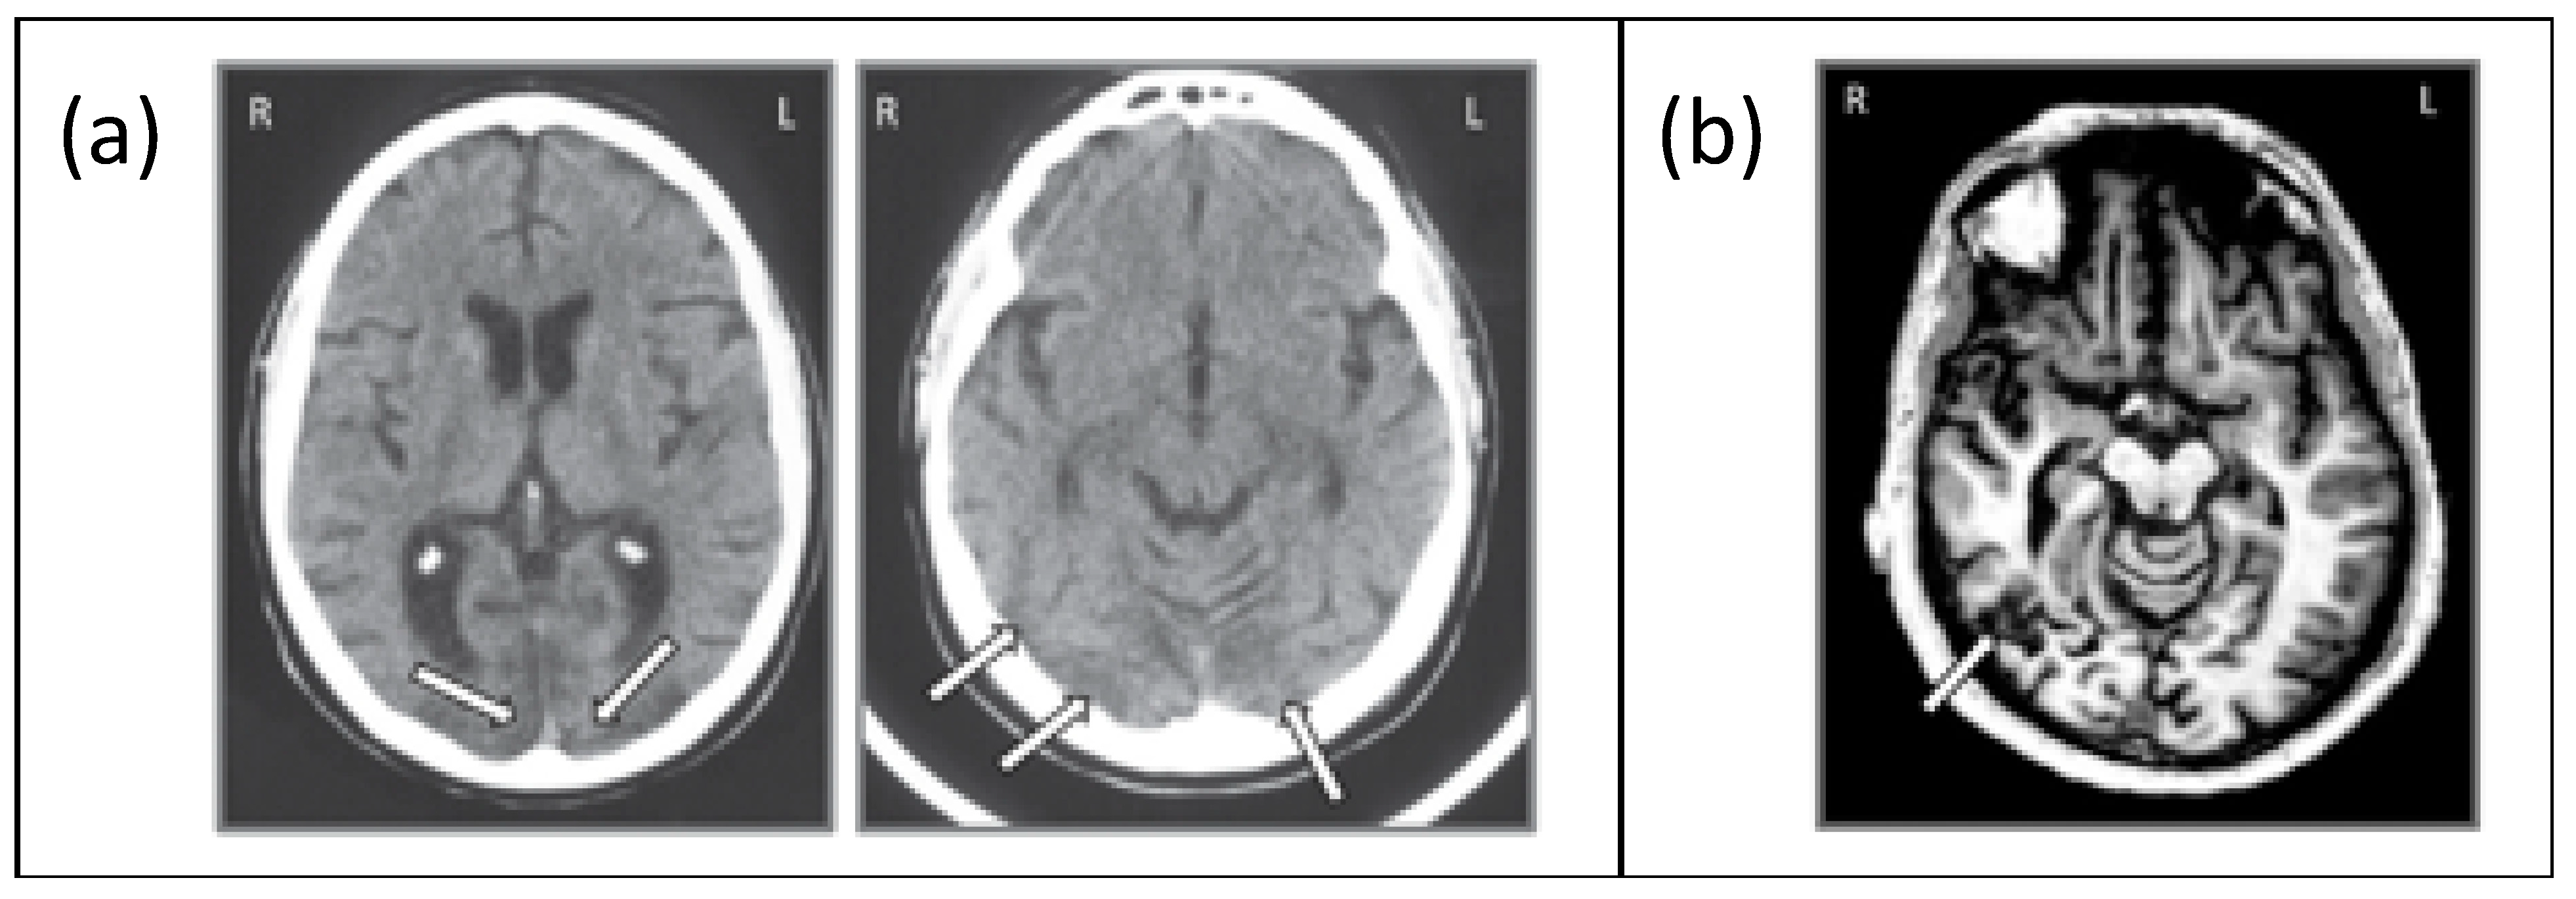

2.1. Participants